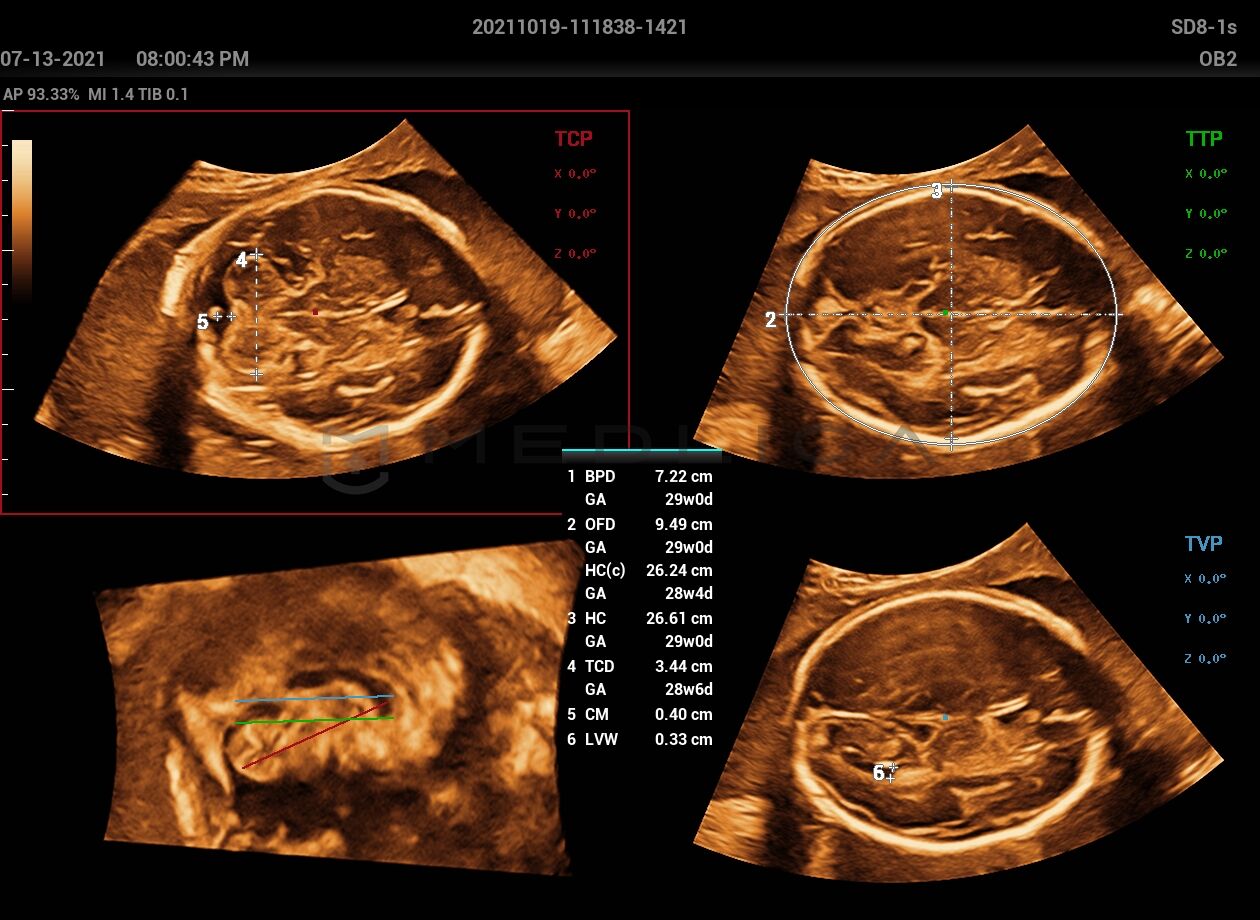

• Полностью автоматическое распознавание срезов, 4 стандартных среза ЦНС

• Высокоточные измерения, 6 часто используемых фотометрических параметра

При нажатии на трехмерное изображение мозга плода незамедлительно будут получены

стандартные сканируемые плоскости ЦНС:

• MSP — интеллектуальная медиальная сагиттальная плоскость

• TCP — трансцеребральная плоскость

• TTP — трансталамическая плоскость

• TVP — трансвентрикулярная плоскость

набор соответствующих анатомических измерений:

• BPD — обмер и вычисление бипариентального размера головы

• HC — окружность головы

• OFD — лобно-затылочный размер головы

• TCD — межполушарный размер мозжечка

• CM — ширина большой цистерны

• LVW — ширина боковых желудочков